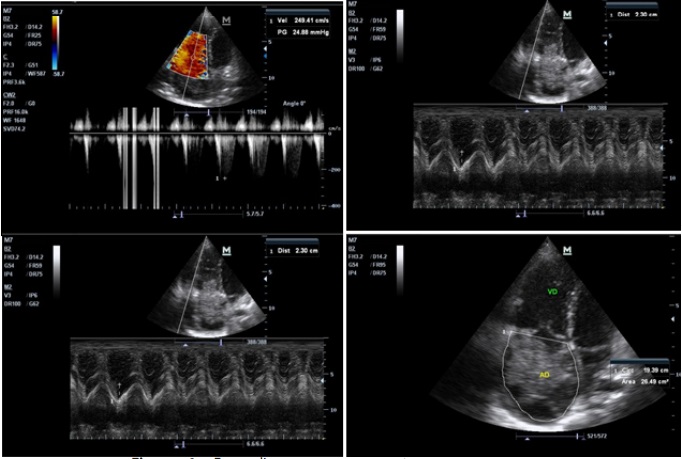

Presentación del caso

Paciente femenina escolar de 9 años de edad sin antecedentes patológicos personales, se encontraba asintomática hasta aproximadamente un día previo a su ingreso, decide ir a consulta médica cuando inicia cuadro de dolor abdominal de inicio en región epigastrio que se irradia a región lumbar de moderada a gran intensidad, tipo pungitivo continuo, acompañado de alzas térmicas cuantificadas de 38°C y un cuadro clínico persistente e incremento del dolor en región de flanco derecho, anorexia, tos no productiva, no cianotizante y no emetizante. Presenta hallazgos patológicos al examen físico, en relación al aspecto respiratorio se evidencia leve retracción supraesternal, campos pulmonares se ausculta crépitos aislados en región subescapular derecho. En relación al aspecto cardiovascular; taquicárdica con frecuencia cardiaca de 128 lpm, presión arterial 100/70 mmHg, a la auscultación con soplo sistólico audible en los 4 focos de auscultación con intensidad II/VI. Exámenes complementarios con hemograma que reporta leucocitos de 11,900 mm 3 a expensas de segmentados 84%, hemoglobina de 15 g/dl y hematocrito 45,3%; pCr de 61mg/dL, gasometría arterial con acidosis metabólica compensada pH: 7,49; pCO2: 20,1; pO2: 89,4; HCO3 13; radiografía de tórax donde presenta infiltrados alveolares basal derecho y cisuritis, sugerente de proceso neumónico basal derecho. Se realiza ecografía abdominal que reporta hallazgo compatible en primer término con endocarditis bacteriana sin descartar tumor auricular (mixoma), hígado con discreto refuerzo periportal, vesícula con presencia de microlitiasis biliar, neumonía basal del lóbulo inferior derecho. Se indica cobertura antibiótica, por sospecha de tromboembolismo pulmonar inician enoxaparina y solicitan dímero D que reporta 4763. Se solicita ecocardiograma ( Figura 1) que reporta crecimiento de cavidad derecha, masa heterogénea móvil de 8,5 x 6 cm a nivel de la aurícula derecha que prolapsa en forma intermitente hacia la cavidad ventricular compatible con mixoma, índice cardiotorácico de 0,6 mm e hipertensión pulmonar leve a moderado.

Es valorada por cirujano cardiovascular que realiza el abordaje diagnóstico, solicita una TAC general para descartar posibles diseminaciones. Basándose en los datos obtenidos, en primera instancia se decide tratar la neumonía basal, a su alta médica por neumología se programa intervención quirúrgica bajo circulación extracorpórea, se realiza auriculotomía derecha y se observa una gran masa de color rojizo pardo que ocupa gran parte de la aurícula derecha, bilobulada, con el segundo lóbulo de aspecto amarillento, móvil, que penetraba en el ventrículo derecho a través de la válvula tricúspide ( Figura 2), con implantación en el tabique interauricular.